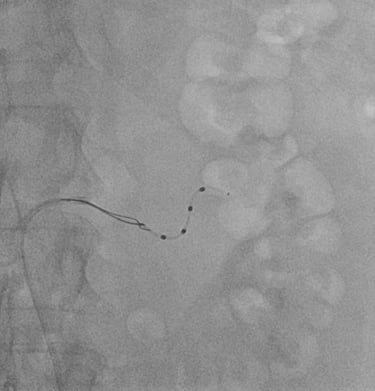

ANALISI DELLA RISERVA DI FLUSSO CORONARICO

Analisi della Riserva di Flusso Coronarico (“Fractional Flow Reserve” o “Pressure Wire”): si tratta di una metodica che, in sala di emodinamica, consente di misurare la pressione sanguigna all'interno delle arterie coronariche ed e’ utile per distingure le stenosi che devono essere trattate con stent da quelle che non ne hanno bisogno.